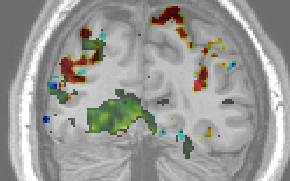

Zero-sum Morlet wavelets improve the fit of first order descriptors to an extent that they compete with second order features in some regions, but are outperformed in others: As can be seen in Fig. 1, there exist spatially contiguous regions largely outside commonly mapped retinotopic areas, in which adding second layer scattering coefficients is beneficial to the model.

We find that an overwhelming majority of the voxels that are well-modelled using first order invariant scattering descriptors is largely better modelled using second order invariant scattering descriptors. The scatterplot 5 indicates this clearly. A Wilcoxon signed rank test provides a confirmation (). Figure 4 shows the localisations of well modelled voxels together with regions that display a high sensitivity to retinotopy. One observes that many voxels outside the low-level ventral visual areas are well modelled by the scattering transform. This includes dorsal regions (up to the intra-parietal sulcus), lateral occipital and medio-temporal regions, and not necessarily retinotopic regions; more precisely several foci are found in V1/V2, and more so in V3 and V4. Blue indicates regions where adding second order features to the first order features does not result in a predictive performance gain. Red indicates regions where one observes a performance gain by adding second order features. The regions were coloured red if the performance gain was greater than of explained variance and blue if the performance gain was or performance decreased. We noticed that the regions that display a strong sensitivity to layer 2, as well as those that actually discriminate between textures, are confined to some foci, the location of which is highly reproducible across sessions and even across subjects.